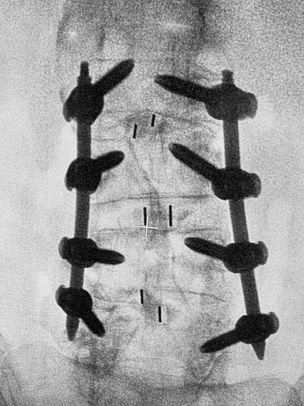

After a thorough diagnosis, the doctor decided to perform a minimally invasive lumbar spinal neurosurgery under a microscope. This surgery involved Transforaminal Lumbar Interbody Fusion (TLIF) at the L2/3, L3/4, and L4/5 levels of the lumbar spine. The primary goal of the surgery was to correct spinal deformities caused by joint dislocation and/or degenerative scoliosis, thereby improving spinal stability and treating lower back pain, in addition to decompressing the compressed spinal nerves.

The surgery, lasting 9.5 hours, required meticulous skill and patience. After the surgery, the patient only needed a 24-hour hospital stay before being discharged. Postoperatively, there was a significant reduction in lower back pain and sciatica. The numbness and weakness in the legs also showed notable improvement. Most reassuringly, his bladder and bowel functions gradually returned to normal.